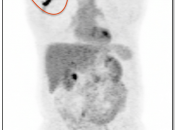

Extravasation of Injected FDG

FDG is injected intravenously. As many cancer patients have challenging venous access issues, partial extravasation of FDG during injection is not uncommon (an estimated 10% of patients have evidence of extravasation on their PET images).

Extravasation of FDG at the time of the intravenous injection can result in false positive interpretations due to:

- Focal intense uptake at the injection site.

- Linear uptake along the lymphatic channels within the arm (appearing as long vessels).

- Focal uptake in small ipsilateral axillary nodes.

If these nodes are enlarged, be cautious before dismissing them as “injection-related”. We have seen more than one case of a radiologist calling axillary nodes “injection-related”, when the patient was injected in the opposite arm.

If the volume of extravasation is large enough, it can result in a significant reduction of circulating FDG available for tumoral uptake, resulting in false negative results (“Sponge Effect”, discussed here).